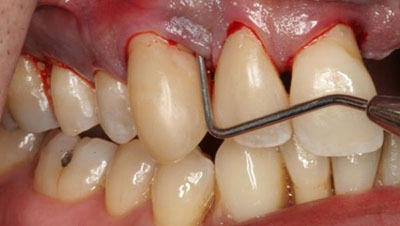

Обязательно измеряют глубину зазора между десной и зубом. Такая несложная процедура помогает определить масштаб поражения. Для этого применяют пародонтальную пробу, которая помещается между зубом и десной. Таким способом обследуют каждый зуб, а совокупность результатов даёт пародонтограмму.